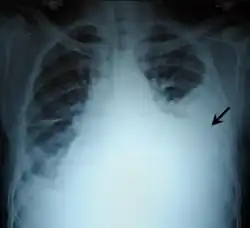

Chest X-ray

Two chest X-rays: left showing a massive left-sided hemothorax; right showing a massive right hemothorax

A chest X-ray is the most common technique used to diagnosis a hemothorax.[23] X-rays should ideally be taken in an upright position (an erect chest X-ray), but may be performed with the person lying on their back (supine) if an erect chest X-ray is not feasible. On an erect chest X-ray, a hemothorax is suggested by blunting of the costophrenic angle or partial or complete opacification of the affected half of the thorax. On a supine film the blood tends to layer in the pleural space, but can be appreciated as a haziness of one half of the thorax relative to the other.[5] A small hemothorax may be missed on a chest X-ray as several hundred milliliters of blood can be hidden by the diaphragm and abdominal viscera on an erect film. Supine X-rays are even less sensitive and as much as one liter of blood can be missed on a supine film.[24]